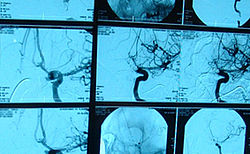

Dem Gefäßzentrum Flensburg steht für seine Aufgaben u.a. ein hochmoderner Hybrid-Operationssaal (OP) zur Verfügung. Die Besonderheit dieser OP-Räumlichkeiten ist, dass unter den sterilen Bedingungen eines OP eine hochleistungsfähige automatisch im Raum verfahrbare Röntgenanlage installiert ist, die optimale Behandlungsmöglichkeiten bei Patienten mit Gefäßerkrankungen eröffnet.

Insbesondere bei komplexen Erkrankungen der Hauptschlagader im Brust- oder Bauchraum, aber auch in allen anderen Regionen des Körpers, können minimal-invasive Kathetertechniken mit anderen operativen Techniken in einem Eingriff kombiniert werden. Behandlungstechniken, die vor wenigen Jahren noch gar nicht möglich waren, können so mit vergleichsweise erheblich reduzierter Belastung für den Patienten durchgeführt werden.